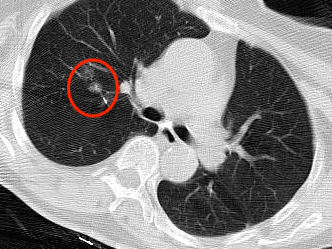

近年来,贵州航天医院各科室紧跟医学前沿,不断强技术、补短板,大力开展新技术、新项目,完成了许多高精尖、高难度、本地区“首例”的技术,填补了医院医疗技术空白,满足了群众日益增长的医疗需求。 贵州航天医院呼吸与危重症医学科是贵州省内呼吸疾病治疗规模最大,诊疗项目最全的呼吸疾病品牌科室,呼吸介入技术达到了全国先进水平,在贵州省内处于领先的地位。 本期,我们将为大家带来呼吸与危重症医学科特色技术——氩氦刀冷冻消融技术治疗肺癌、高危肺结节。 案例分享 患者在体检时发现右肺结节(10mm),就诊于当地我院一专科联盟合作医院,但因当地医疗条件有限,患者通过专科联盟绿色通道前往我院就诊,入院后,通过经皮肺穿刺活检,病理诊断为右肺原位腺癌,科室立即组织专家开展肺结节多学科会诊(MDT),为患者制定诊疗方案。 经充分的沟通下,患者及家属拒绝手术切除。科室再次严格讨论评估,患者情况满足氩氦刀冷冻消融术指征,再次将治疗方案与患者及家属沟通同意后,为患者制定并成功实施氩氦刀冷冻消融术。 冷冻消融术中 术后,患者定期复查,恢复效果良好。 术前 术后即刻 术后1月(反应性增大) 术后6月(纤维条索) 术后12月(纤维条索变细) 什么是氩氦刀冷冻消融技术 氩氦刀冷冻消融技术是一种先进的微创超低温冷冻消融肿瘤的医疗技术,它利用氩气和氦气的快速温度变化特性,实现对病变组织的精准冷冻和复温,以达到消融和破坏肿瘤细胞的目的。 氩氦刀冷冻消融技术原理 氩氦刀冷冻消融技术基于焦耳-汤姆逊效应,通过氩气和氦气的快速交换实现局部组织的超低温冷冻(-140℃到-190℃)和快速复温(20℃到45℃),当氩气通过金属杆尖端的蒸发器时,其气压突然降低,会大量吸收周围的热量,使金属杆尖部的气温迅速下降到超低温;随后,氦气在极短的时间内使组织迅速复温,通过热胀冷缩的原理,使肿瘤细胞爆裂。 (一)直接杀伤( 靶区冷冻消融效应) 1.快速冷冻(降温段):细胞内冰晶快速生长并撕裂细胞,导致细胞损坏。 2.慢速冷冻(低温段):细胞外冰晶生长导致水渗出细胞,造成细胞脱水。 3.升温:水迅速进入细胞,导致细胞涨破。 (二)间接杀伤( 冷冻的血管栓塞效应) 病灶区域快速冷热交替,引起微血管细胞脱水、蛋白质变性、微血管损伤、 冰晶及微血栓在微血管内形成,导致血小板聚集、血管栓塞, 局部细胞缺血坏死。 (三)抗肿瘤免疫( 冷冻免疫激活效应) 随着肿瘤细胞的破裂和坏死,促使肿瘤免疫调节因子停止分泌,逆转免疫抑制状态;可调控表面抗原,促进淋巴细胞增殖,提高身体抗肿瘤免疫能力。 氩氦刀冷冻消融技术优势 (一)精准度高:通过精确的靶点定位和温控技术,可实现对病变组织的精准冷冻和复温,避免损伤正常组织。 (二)微创治疗:对周围正常组织的热损伤小,无需开胸开腹,仅有一个针孔,恢复快,几乎无疤痕。 (三)适应症广:肺腺体前驱病变(癌前病变)、甲状腺结节、乳腺结节等;多原发磨玻璃肺结节,因各种原因不适合手术的早期肺癌、肝癌等;内科治疗无法控制的少发转移瘤等。 (四)可重复治疗:由于冷冻治疗对身体的创伤和痛苦较小,可以多次重复进行治疗,这对巨大的肿瘤和多发的肿瘤尤其适用。 (五)无毒性:冷冻治疗是以物理方法杀灭肿瘤,不向体内注射任何药物,避免外科手术、化放疗等对身体带来的巨大创伤和毒副作用,能有效减轻患者肿瘤负荷和痛苦,因此与化放疗、分子靶向药物等治疗方式相比属于无毒治疗。 氩氦刀冷冻消融技术对于早期肺癌、高危结节,可作为手术的替代治疗。对于晚期较大的肿瘤可作为姑息治疗,增强综合治疗的效果,可减少肿瘤负荷,减轻症状,提高生活质量,延长生存时间。 近年来,随着医学影像技术发展和肺癌筛查的广泛开展,肺内结节的检出率显著提高。无论肺内磨玻璃结节还是实性结节,单发或多发,都需要引起重视,定期复查,动态观察结节变化,如有需要请积极治疗。 贵州航天医院 呼吸与危重症医学科专家团队 廖江荣 国务院政府特殊津贴专家、遵义市呼吸疾病临床医学中心学科带头人、二级教授、主任医师 学术任职: 亚洲冷冻治疗学会副主席 第二届中国医药教育协会介入微创专业委员会呼吸分会副主任委员 中国抗癌协会肿瘤微创治疗专业委员会常务委员 中国防痨协会结核病转化医学专业分会常务委员 第一届中国人体健康科技促进会呼吸介入专委会常务委员 中国医疗保健国际交流促进会结核病学分会第三届委员会常务委员 中国抗癌协会肿瘤微创治疗专业委员会粒子治疗学组第四届委员会委员 中国结核病防治综合质量控制专家指导委员会委员 “西部呼吸介入联盟”副理事长 专业擅长: 呼吸系统(肺)疑难病的诊断及危重病的抢救,呼吸系统(肺)感染性、疑难性疾病介入快速诊断(ROSE),尤其在肺癌、肺小结节早期诊断,肺癌微创综合靶向治疗,难治性、复治性、重症肺结核诊疗,硬质支气管下复杂性气道狭窄诊治,纤支镜介入治疗气道肿瘤、结核、气道狭窄(球囊扩张、支架植入、高频电刀、氩气刀、冷冻、灌洗、注药、微波消融),间质性肺疾病的诊疗上具有极高水平;带领团队勇于创新,在贵州省率先开展多项新技术、新疗法,如CT引导下及纤支镜下I125粒子植入及CT引导下微波、冷冻消融介入治疗肺癌等多项新技术,带动了贵州省肺部疾病的介入治疗水平提高。 唐永江 四川大学华西医院 呼吸与危重症医学科 副主任医师 呼吸危重症医疗组长 香港中文大学博士 美国康奈尔大学访问学者 贵州航天医院 呼吸与危重症医学科 学科带头人 主要从事呼吸危重症(特别是呼吸重症感染)的临床及科研工作。 PCCM专培结业医师 中华医学会呼吸病学分会呼吸危重症学组秘书 中华医学会呼吸病学分会ECMO工作组成员 四川省医学会呼吸病学专委会介入学组委员兼秘书 发表文章20余篇,主持及参与多项国家自然科学基金及省卫健委基金。 蒋 婷 呼吸、感染党支部书记,呼吸与危重症医学科主任,副主任医师 专业擅长:从医20余年,在呼吸系统疾病、介入呼吸病学、肺部结核、肺部肿瘤等方面具有丰富的临床经验和专业技能,尤其是慢性阻塞性肺疾病、支气管扩张、肺结核、耐药肺结核、肺癌、胸腔积液等肺部疾病的诊治、微创介入、危重病患者抢救。 现任中国防痨协会人兽共患结核病专业分会委员,中国女医师协会第一届介入专业委员会委员,贵州省基层呼吸疾病防治联盟-间质性肺疾病联盟委员,贵州省防痨协会第七届理事会理事,贵州省中西医结合学会呼吸专业委员介入呼吸病学组委员,贵州省遵义市中医药学会中西医结合肺病(呼吸)分会副主任委员,贵州省遵义市中医药学会中医肿瘤专业委员会常委;发表论文数篇,参与并主持多项科研项目。 王 云 中共党员,呼吸与危重症医学科一病区副主任,副主任医师 专业擅长:擅长呼吸系统常见病及疑难危重症、介入呼吸病学、肺部肿瘤疾病的诊治,尤其擅长快速现场评价(ROSE)技术。 贵州省中西医结合学会呼吸专业委员会介入呼吸病学组委员,遵义市中医药学会中西医结合肺病(呼吸)分会委员,贵州省中西医结合学会第六届呼吸专业委员会委员。 李桂凤 中共党员,呼吸与危重症医学科三病区主任,副主任医师 专业擅长:从事呼吸系统疾病、结核病学、介入呼吸病学、肿瘤综合治疗、呼吸康复等临床工作20余年,擅长呼吸内科常见病、多发病及疑难重症危重病症的诊治,尤其对重症疑难结核及耐药结核病、介入治疗(肺)呼吸系统疾病、呼吸危重病抢救等方面具有较高诊疗水平。 中国防痨协会非结核病专业委员会委员,贵州省中西医结合学会第六届呼吸专业委员会委员,贵州省康复学会睡眠障碍康复专业委员会委员,遵义市呼吸内科医疗质量控制中心委员,遵义市落实民生实事结核病筛查阅片专家组成员;主持及参与实用新型专利3项。 周裕祥 中共党员,呼吸与危重症医学科四病区主任,副主任医师 专业擅长:经皮肺介入、经血管介入诊疗技术。 贵州省中西医结合学会呼吸专业委员会介入呼吸病学组常务委员,中国医师协会呼吸医师分会介入呼吸病学工作委员会呼吸病血管介入学组委员,贵州省中西医结合学会呼吸学分会委员,遵义市医学会放射肿瘤治疗学分会委员,中国医药教育协会介入微创呼吸分会委员,北京健康促进会中青年专家委员会胸部疾病精准活检分委会委员;曾赴重庆医科大学RICU、珠海市人民医院介入科进修学习。 杨 芳 中共党员,呼吸与危重症医学科内镜中心主任,副主任医师 专业擅长:从事临床工作约20年,对呼吸危重病的救治有独到的见解,尤其擅长呼吸系统疾病的介入诊疗,对呼吸内镜下的诊治及经皮肺穿刺诊疗技术具有丰富的临床经验。 亚洲冷冻治疗学会委员,中国医药教育协会介入微创呼吸分会委员,西南结核病医院联盟第二届委员会秘书/委员,贵州省中西医结合学会第六届呼吸科专业委员会委员,贵州省中西医结合学会呼吸专业委员会介入呼吸病学组秘书,贵州省中西医结合学会呼吸专业委员会基层康复学组副组长,贵州水利电力医学科学技术会高原医学分会委员,遵义市中医院学会中西医结合肺病(呼吸)分会秘书/常务委员,遵义市医学会肿瘤学分会(第二届)委员,遵义市医学会放射肿瘤治疗学分会第二届委员;主持及参与科研课题多项,参编著作《呼吸内镜操作技术规范》、《介入结核病学》,发表论文数篇。 贵州航天医院 呼吸与危重症医学科简介 贵州航天医院呼吸与危重症医学科以呼吸危重症和介入呼吸病学为强力推手,以肺部感染性疾病及肺癌、肺小结节的早期精准诊疗、慢性呼吸疾病康复治疗为特色,以人才团队建设为核心的科室发展模式,现已成为贵州省内呼吸疾病治疗规模最大、诊疗项目最全的呼吸疾病品牌科室。是贵州省医学重点学科、临床医学重点专科建设单位,遵义市首批呼吸重点学科、重点专科建设单位。是国家卫健委能力建设和继续教育肿瘤微创介入建设中心、贵州省县级医院微创介入培训中心、遵义市呼吸疾病临床医学中心。是国家呼吸医疗质量控制与管理哨点医院、遵义市呼吸内科专业医疗质量控制中心。是中国医药教育协会介入微创呼吸分会呼吸介入技术培训中心单位;国家卫健委海医会呼吸分会ROSE专委会“诊断性介入肺脏病学快速现场评价”培训基地;中国肺癌防治联盟“贵州航天医院肺结节诊治”分中心,中国人体健康科技促进会呼吸介入技术培训基地,贵州省中西医结合会呼吸学分会呼吸介入专委会主委单位。 基本情况 平均每年开展气管镜诊疗约4000例,经皮肺穿刺介入诊疗近千例,开展的项目包括经支气管镜(软、硬)下冷冻、氩气刀、高频电刀、球囊扩张、支架置入、超声内镜诊疗等气道介入诊疗技术,经皮肺穿刺活检及肿瘤消融术(微波、冷冻)、ROSE技术、内科胸腔镜诊疗及经血管介入诊疗技术,且多项呼吸介入诊疗技术在省内处于领先水平。 诊疗范围 专科擅长:致力于呼吸系统感染性、疑难性疾病的介入快速精准诊疗;肺癌与肺小结节早期精准诊疗水平项目提升。擅长呼吸系统(肺)疑难病的诊断及危重病的救治,尤其是肺癌、肺小结节的早期诊断,肺癌综合靶向治疗,肺结核综合诊疗等肺部疾病的介入诊疗在贵州省内处于前沿水平。 肺结节MDT门诊 贵州航天医院呼吸与危重症医学科微创介入诊疗技术已达到国内前列,省内领先水平,是亚洲冷冻治疗学会常务理事单位,并获批成立遵义市肺结节多学科(MDT)微创诊疗中心。 出诊信息 出诊时间: 周一至周五 8:00--12:00;14:00--17:00 出诊地点: 遵义市肺结节多学科微创诊疗中心(MDT)门诊(贵州航天医院呼吸综合楼1楼) 呼吸与危重症医学科与心胸外科、医学影像科、麻醉科等科室建立了多学科(MDT)会诊机制,结合患者情况,通过采取外科手术、冷、热消融等多种治疗手段,帮助患者安全、有效、精准、科学、快速治疗肺结节,单次消融手术时间约半小时左右,几乎没有疼痛,且并发症少,3-5天即可出院,有效减少了患者因开刀手术需长时间恢复的痛苦。 一审一校:周裕祥、黄成成